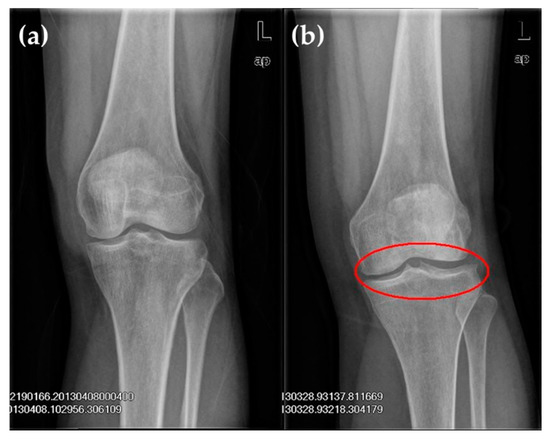

| Grade | X-ray Imaging Features |

|---|---|

| 0 | Normal |

| I | The joint gap is suspected to be narrowed; there may be osteophyma |

| II | Obvious osteophyma; the joint gap is suspected to be narrowed |

| III | Moderate osteophyma; the joint gap is obviously narrowed with sclerotic change |

| IV | Massive osteophyma; the joint gap is obviously narrowed with severe sclerotic lesions and obvious deformities |